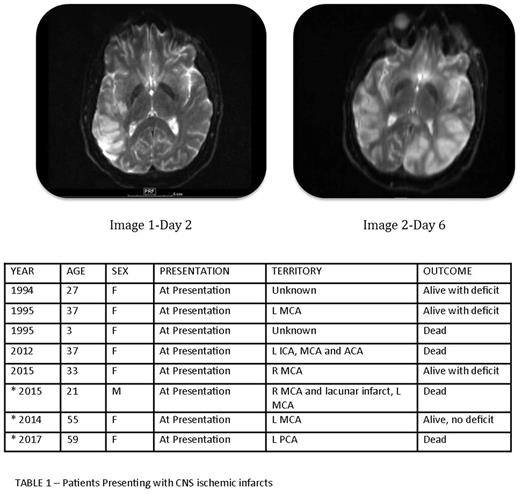

On review of the literature, five cases were described where patients with newly diagnosed APL presented with CNS arterial thrombosis; 3 patients are alive with neurologic deficit and 2 are dead. (Table 1).

Patient 1- 21-year-old male who presented to an outlying hospital with expressive aphasia. MRI scan showed large right temporoparietal infarction. Labs showed WBC 21.6, platelets 9,000, low fibrinogen, elevated PT and elevated d-dimer. High-risk APL was confirmed and ATRA and IV dexamethasone were started. Heparin drip was initiated to decrease risk of further ischemic insult. Worsening neurologic symptoms 4 days later led to a repeat MRI scan, which showed progressive right sided infarct and a new infarct in the left distal territory of the middle cerebral territory and expired shortly thereafter. Images 1 and 2 show infarcts on day 2 and 6 of admission.